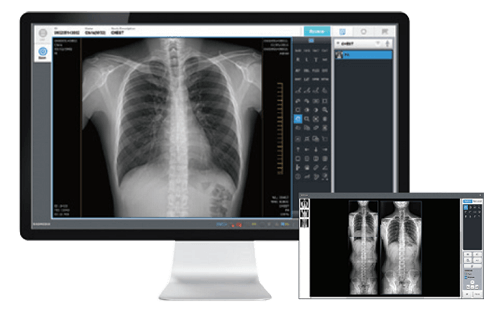

Soluciones para Radiología Digital

Incorpore la última tecnología en Radiología Digital con nuestra gama de Detectores Flat Panels.

Disponibles para Radiología General, Móvil, Mamografía, Neonatología y Fluoroscopía.

Brindamos integración con HIS – PACS centralizados.

Explore nuestra gama de detectores innovadores y mejore la eficiencia y precisión en sus procedimientos radiológicos.

- Amplia variedad, para todas las prácticas.

- Repertorio completo de herramientas.

- La mejor calidad de imagen.

SOFTWARE

Innovador, intuitivo y fácil de usar

Cloud PACS

Almacenamiento de imágenes

Soluciones Avanzadas en la nube.

Procesamiento, medición, comunicación y almacenamiento de imágenes médicas. En cualquier momento y lugar !